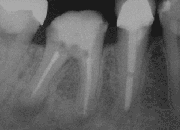

![]() صورة أشعة لسن بعد استئصال قمة الجذر | |